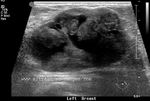

Giant fibroadenoma or Juvenile fibroadenoma

These ultrasound images of the left breast in a 15 yr. old female patient show a large (the mass measured 8.2 cms.), more or less homogenous, well defined mass with posterior acoustic enhancement. These findings suggest a diagnosis of giant fibroadenoma of the left breast. The main differential diagnosis in such a case would be phyllodes tumor. However, phyllodes tumor is seen in females over 30 yrs. of age. Despite the rapid increase in size of the mass, in this case, the potential for malignancy is very low. Ultrasound images are courtesy of Ravi Kadasne, MD, UAE.